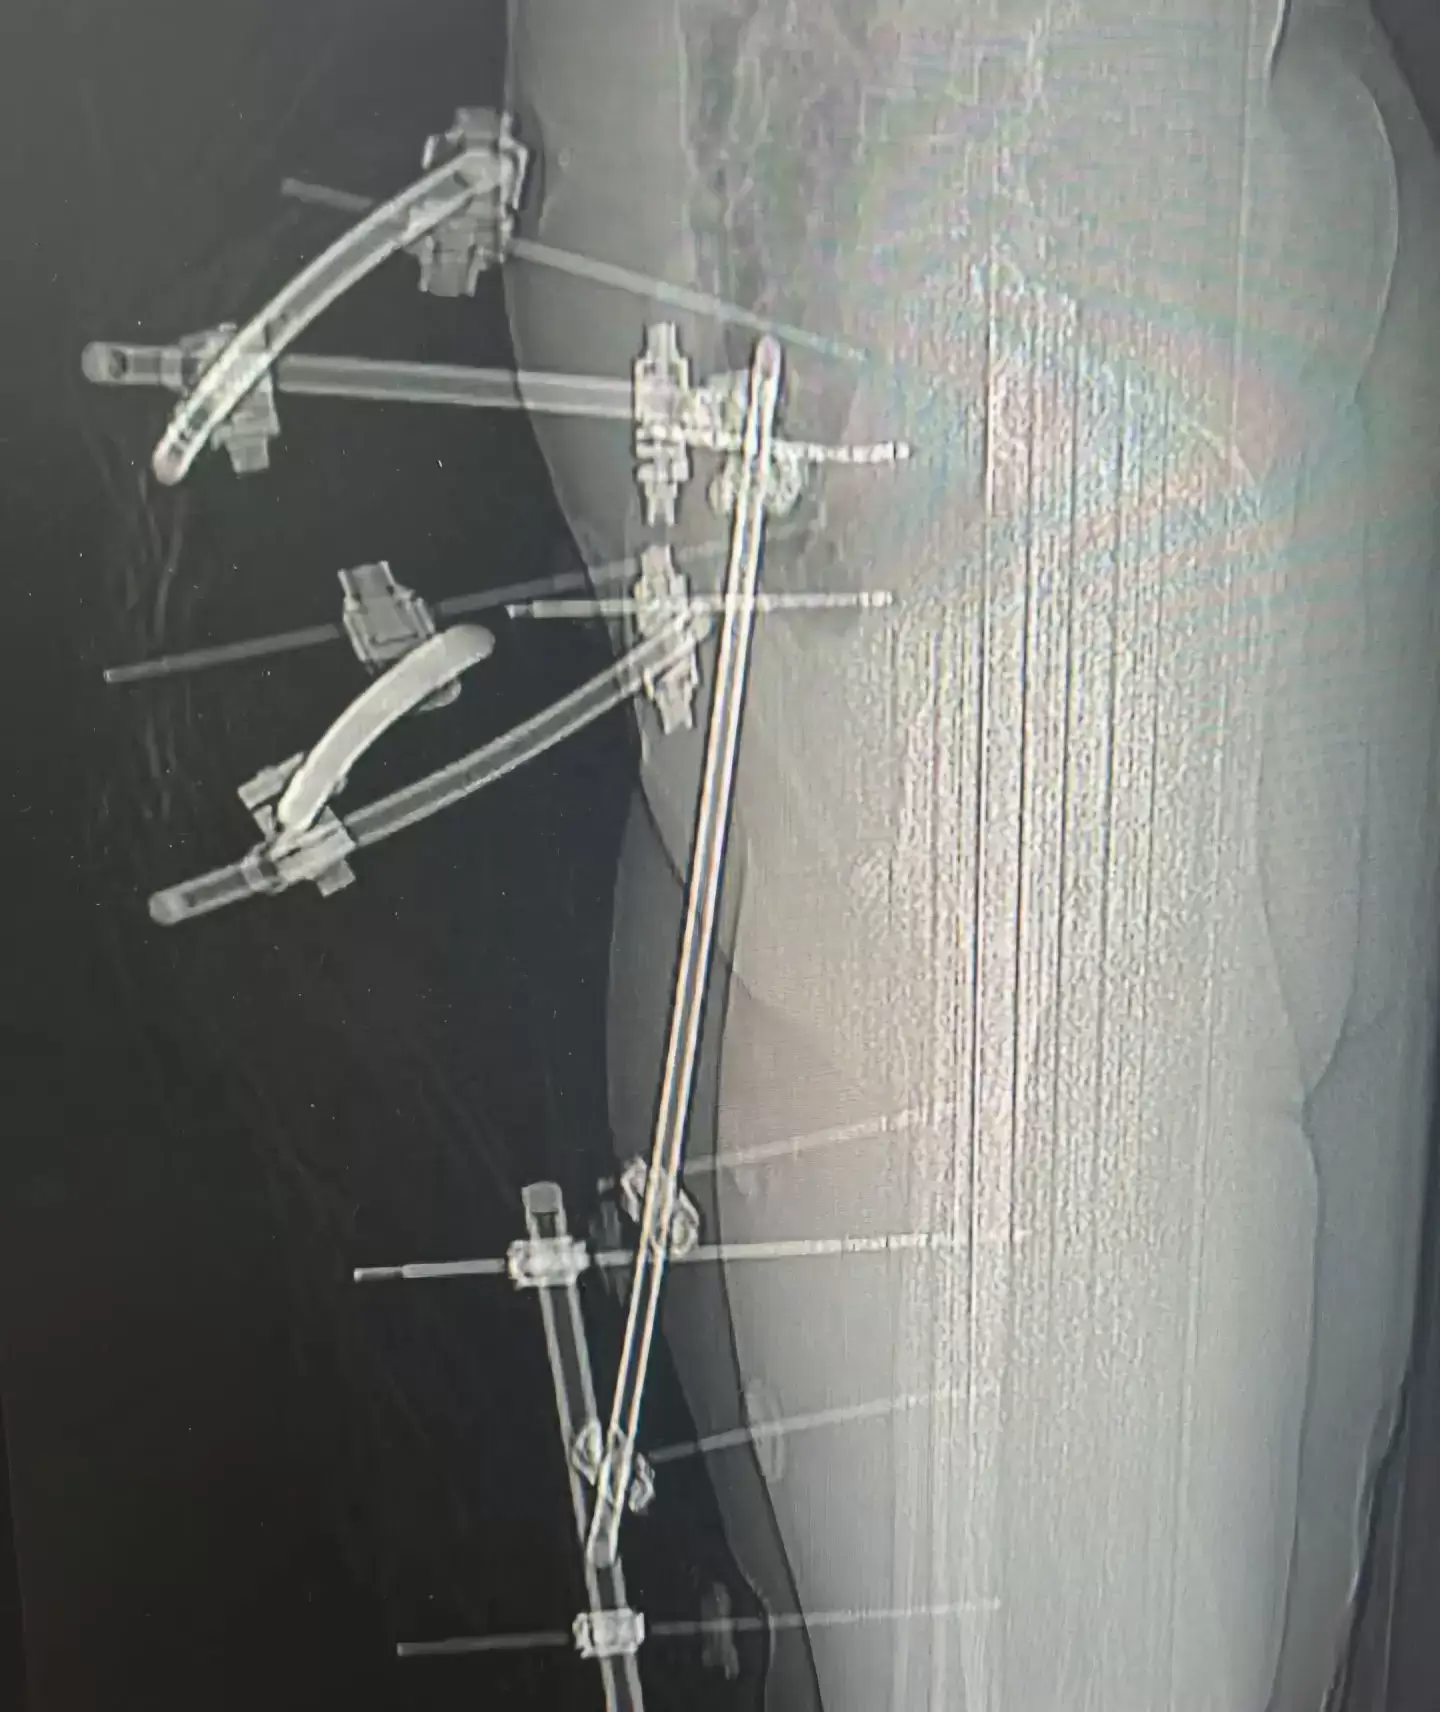

Как сообщает "Вести: Приморье" со ссылкой на Минздрав Приморья, благодаря оперативной и слаженной работе бригады скорой медицинской помощи удалось спасти молодую девушку с крайне тяжёлыми травмами. Пострадавшую экстренно доставили в Спасскую городскую больницу, в травматологическое отделение. Состояние пациентки оценивалось как крайне тяжёлое: травматический шок, открытые переломы костей голени, множественные переломы таза, обширные рваные раны нижних конечностей.

После стабилизации состояния врачи провели сложнейшее оперативное вмешательство — выполнены наружная и внутренняя фиксация переломов таза и голени, лапароскопия для исключения повреждений внутренних органов, а также первичная хирургическая обработка ран. Операция прошла без осложнений», – рассказали специалисты больницы. После этапа реанимации, по согласованию с краевыми медицинскими учреждениями, пациентку перевели в Краевую клиническую больницу №2 для дальнейшей реабилитации.